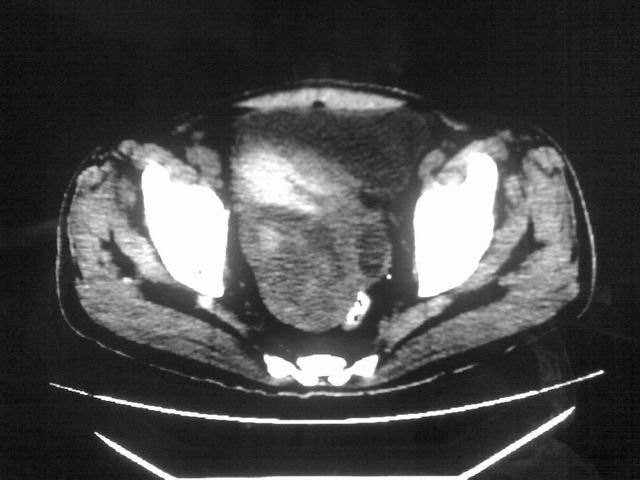

患者m 56岁,盆腔及下腹部胀痛半年,加重1月余,消瘦\中重度贫血.(附:平扫时直肠的高信号为,残留的钡剂).补一下病史:胃镜及纤维结肠镜均无明显异常.

首先是病灶的定位,平扫看很象肠管肿瘤但既然纤维结肠镜正常就可以除外结肠病变,增强成不均匀强化,位于右下腹部应该首先考虑回肠末段占位性病变,1淋巴瘤,2间质瘤,3腹膜后神经原肿瘤待除外,

首先是病灶的定位,平扫看很象肠管肿瘤但既然纤维结肠镜正常就可以除外结肠病变,增强成不均匀强化,位于右下腹部应该首先考虑回肠末段占位性病变,以间质瘤或淋巴瘤可能性大.,

膀胱及直肠间有不规侧的软组织密度影,内密度不均匀。其内有坏死囊变,前列腺及精囊腺,膀胱后壁受浸。结合病史考虑腹膜后肉瘤可能性大。